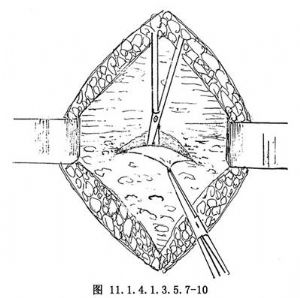

11.2 2.分離腹膜膀胱間隙

同腹膜外剖宮產術,可用側入法或頂入法。於膀胱頂部下1~2cm處橫行切開膀胱筋膜,深達膀胱肌層,切口向兩側延長(圖11.1.4.1.3.5.7-8)。以鉗子提起膀胱筋膜上緣,分離、下推膀胱,先向上分離達膀胱頂部(圖11.1.4.1.3.5.7-9),再向下分離達膀胱腹膜反折(圖11.1.4.1.3.5.7-10)。此處可見臍中韌帶和臍旁韌帶,視其組織厚薄進行切斷縫扎(圖11.1.4.1.3.5.7-11)。